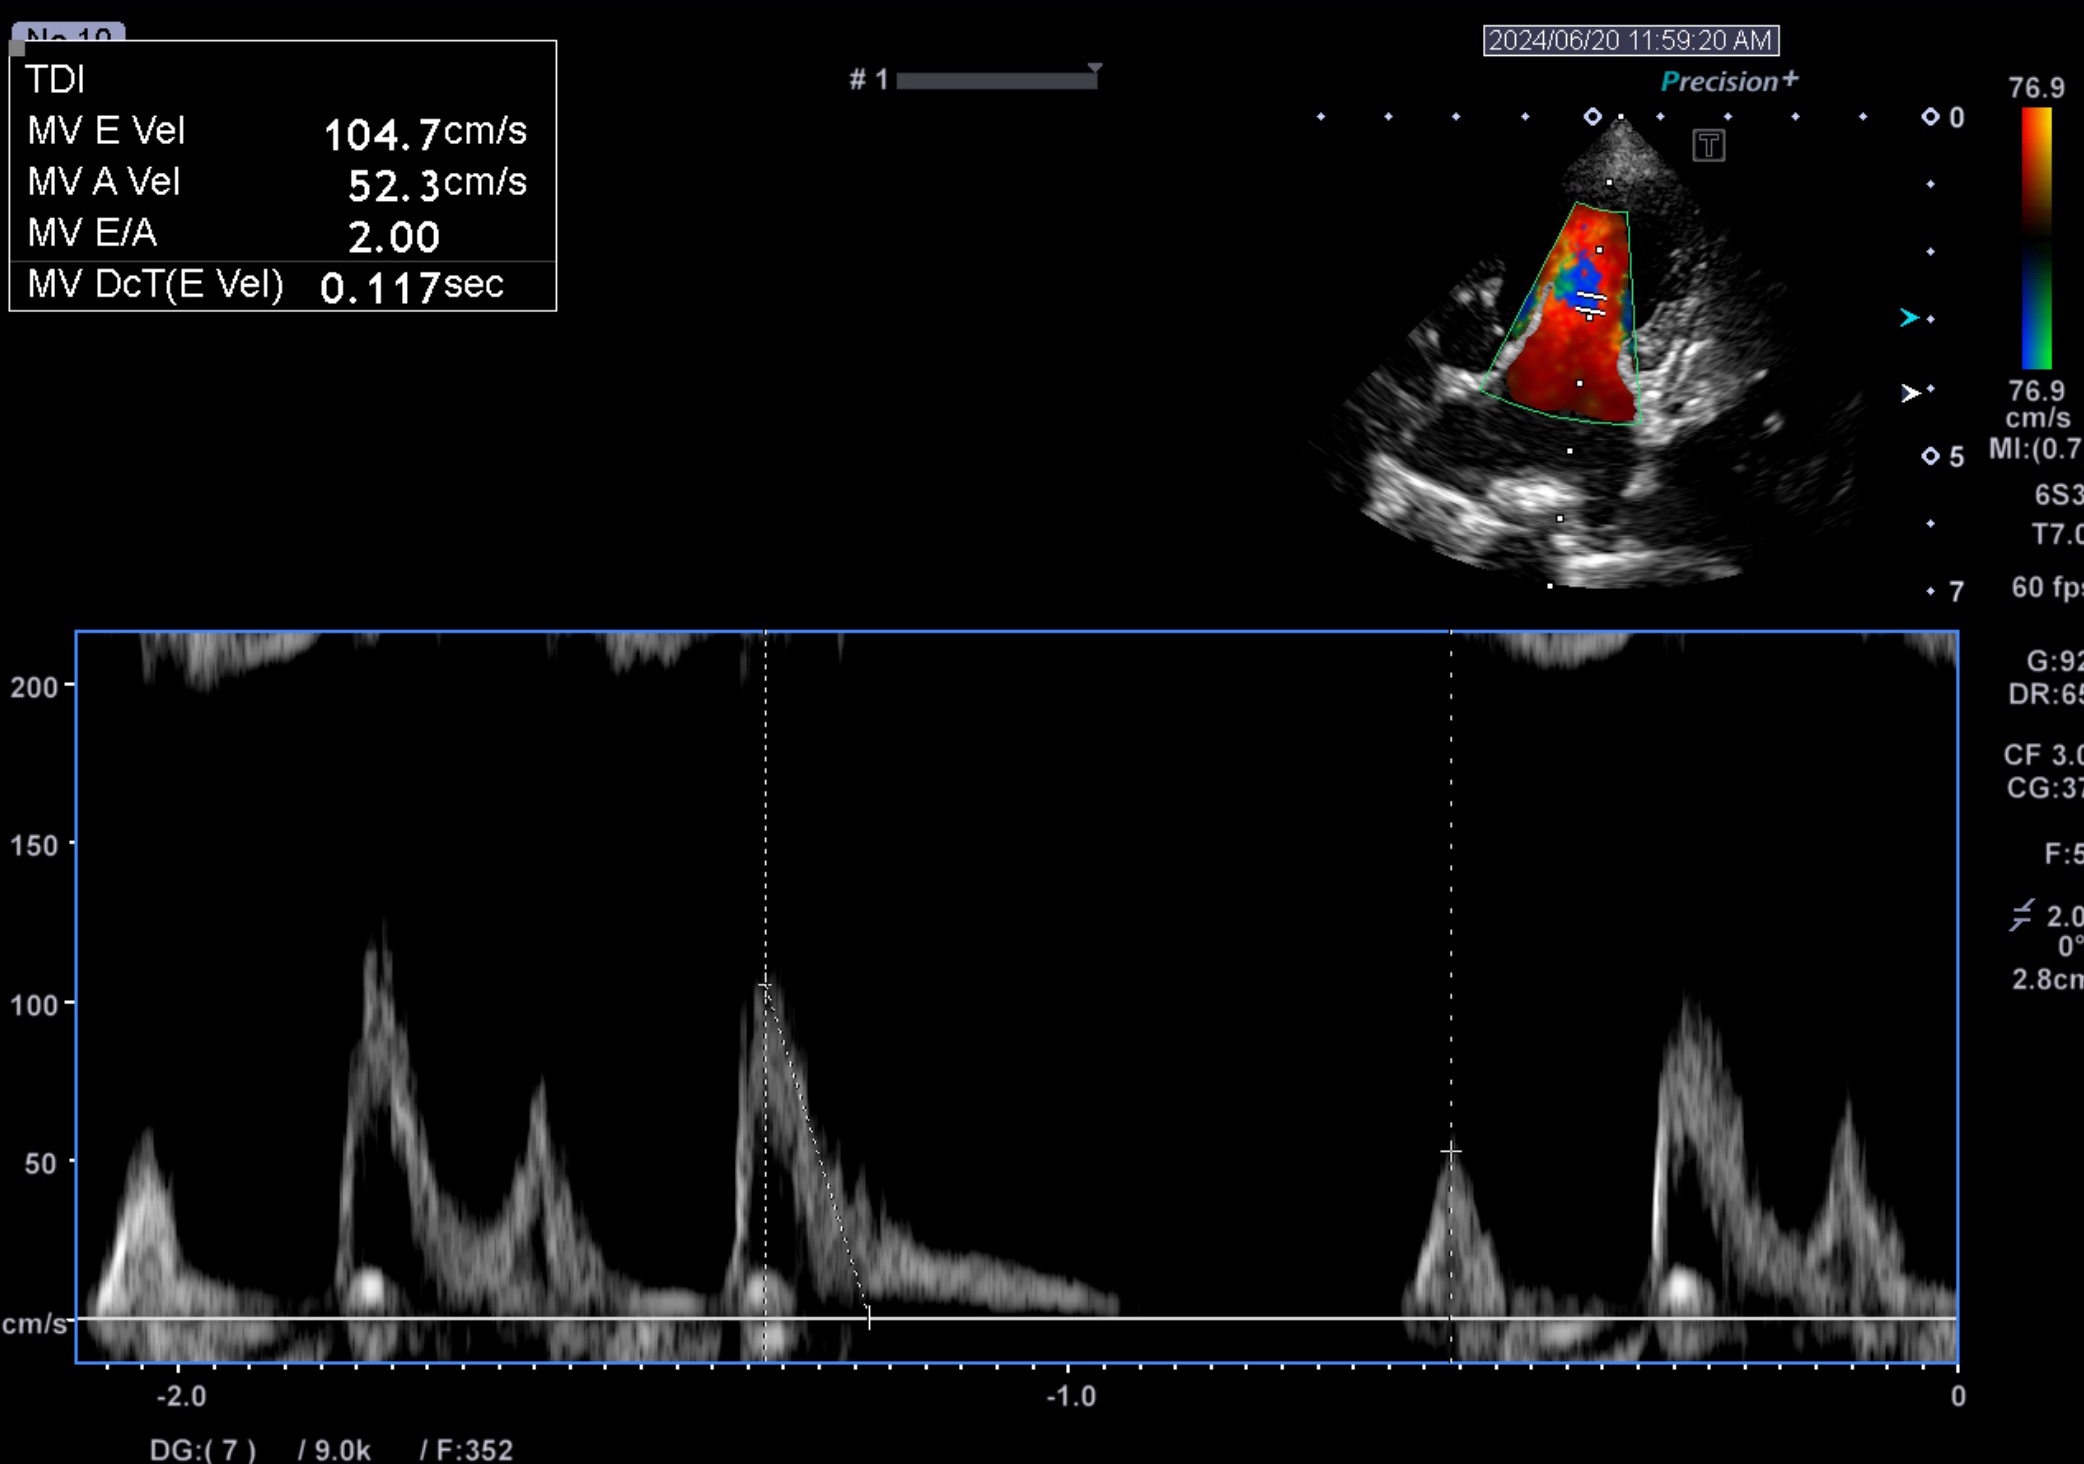

12歳のチワワちゃん。自宅で咳が認められたため来院されました。

聴診にて左側心尖部にLevine Ⅳ/Ⅵの収縮期雑音が認められ、画像検査を実施しました。

臨床学的検査を実施し、僧帽弁閉鎖不全症 (ACVIM stage B2)と診断し、ピモベンダンの内服を開始しました。その後の検診にて、咳の改善、心負荷の改善が認められた。

咳が出る原因の一つとしては、僧帽弁閉鎖不全症が進行すると心拡大、特に左心房の拡大が生じる。本来は心臓と気管支は接していないのだが、左心房が拡大すると左主気管支を圧迫してしまい、それが原因で咳が生じると言われています。